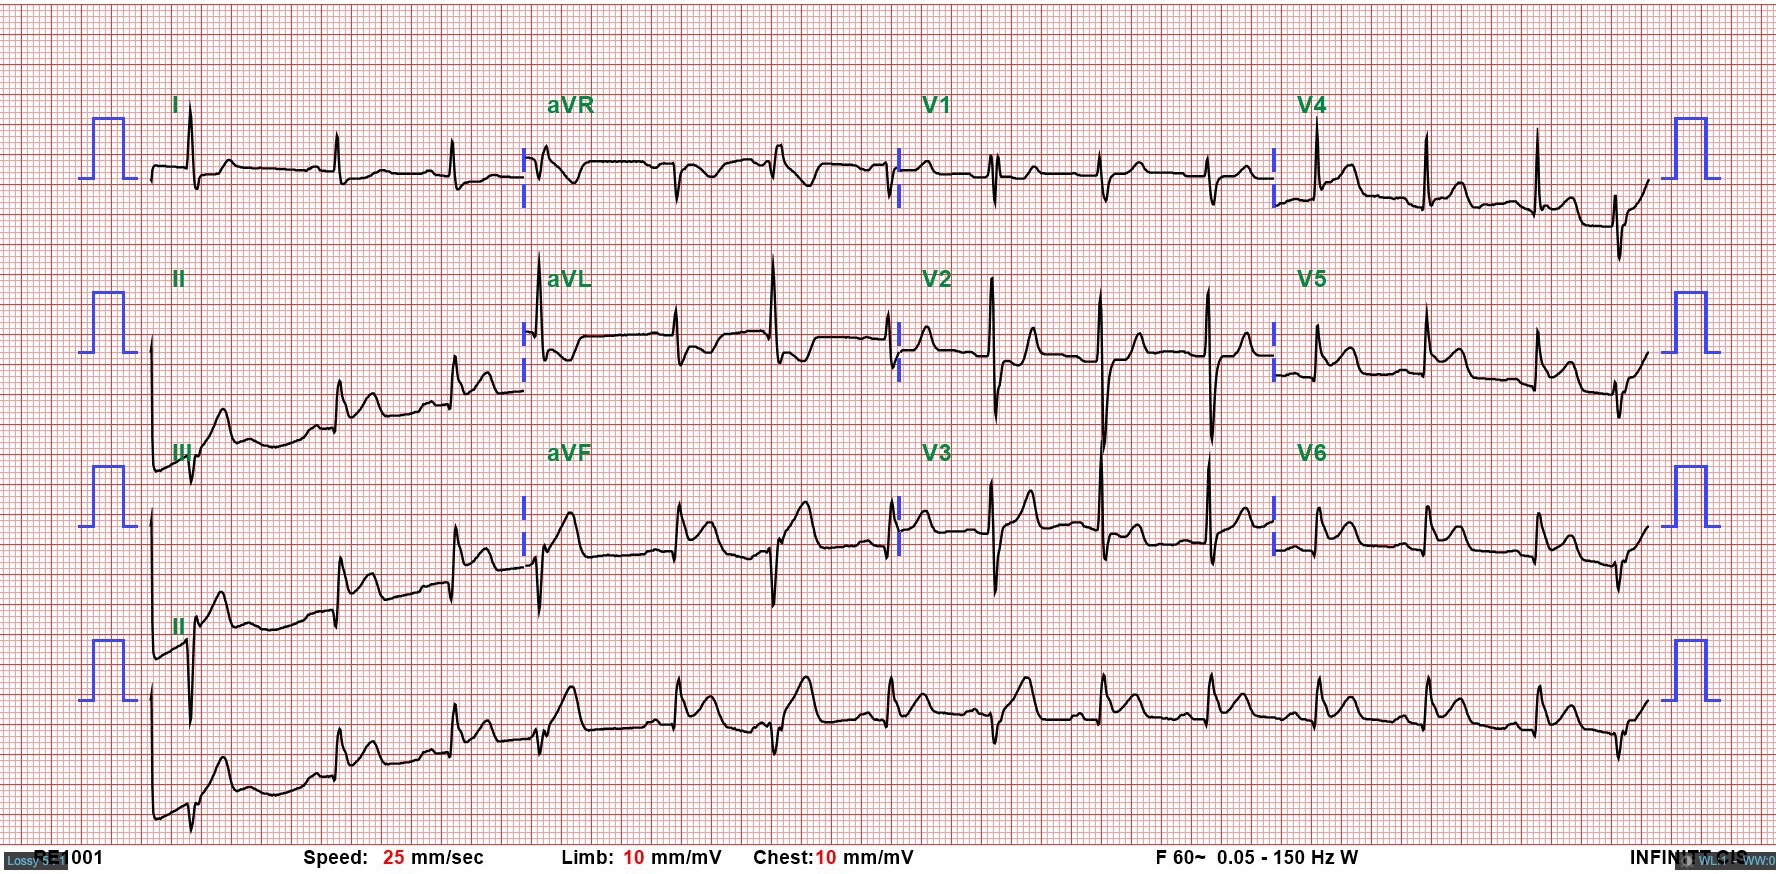

A 42-year-old male, a former smoker with a history of non-ST elevation myocardial infarction (NSTEMI) in 2020, presented with 30 minutes of chest pain and cold sweats. Examination showed stable vital signs, clear breath sounds, and no murmurs. EKG revealed ST elevation in leads II, III, aVF, and V5-V6, with reciprocal changes in leads I and aVL. Echocardiography showed inferior-posterior wall motion abnormalities. Diagnosed with inferior wall STEMI, emergency coronary intervention was arranged.